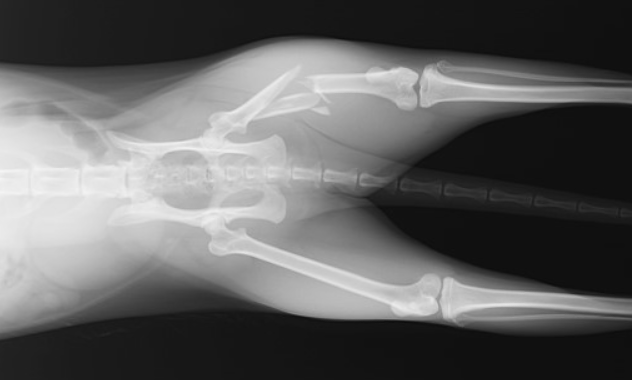

左大腿骨(後ろ足の骨)の粉砕骨折の事例です。外に出る子だったので、交通事故に遭われたのだと思います。

1. レントゲン検査:骨折の種類と場所を正確に確認するためにレントゲン検査が行われます。